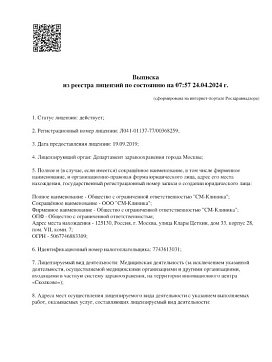

Лицензии